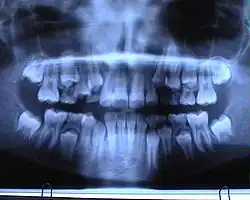

Ein Orthopantomogramm (OPT oder OPG, seltener OPTG), auch Panoramaschichtaufnahme (PSA) genannt, ist eine zweidimensionale Röntgenaufnahme des Ober- und Unterkiefers in Form eines Halbkreises von einem Ohr zum anderen. Es ist ein Standardverfahren der dentalen Radiographie und erlaubt eine diagnostische Röntgenaufnahme der Ober- und Unterkiefer des Menschen, dabei werden alle Zähne, die angrenzenden Kieferbereiche, beide Kiefergelenke und ebenso die rechte und die linke Kieferhöhle abgebildet. Das OPT erfasst ferner den seitlichen Halsbereich, so dass auch Arterienverkalkungen der großen Halsschlagadern diagnostizierbar sind.

In erster Linie dienen OPG-Aufnahmen der Übersicht, demnach einer Grobdiagnostik, beispielsweise ob Zähne verlagert, retiniert oder nicht angelegt sind. Auch Veränderungen des Kieferknochens sind erkennbar und oft der Verlauf des Nervus mandibularis. Zahlreiche Nebenbefunde können erfasst werden. Der mittlere Bereich der Aufnahme wird durch eine verfahrenstechnisch bedingte Überprojektion der Halswirbelsäule speziell im Frontzahnbereich verschattet. Ebenso werden oft die Wurzelspitzen durch eine Überprojektion des knöchernen Gaumens verschattet. Dadurch sind diese Bereiche undeutlich abgebildet und einer präzisen Diagnostik nicht zugänglich.[6]